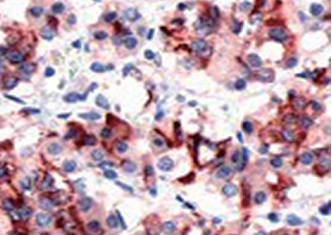

| 預(yù)處理:高pH熱修復(fù) | 陽性部位:細(xì)胞漿 | 陽性對(duì)照:胎盤/垂體瘤 |

| 垂體瘤石蠟切片,用 PRL(GT2161)染色,細(xì)胞漿陽性,DAB 顯色。 | ||